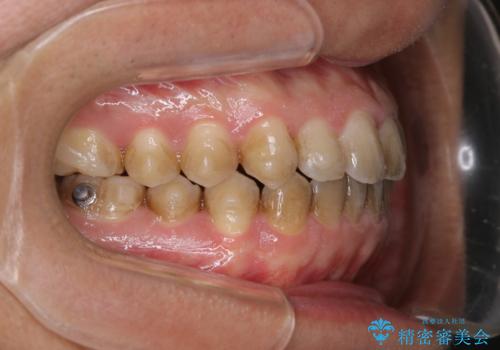

コーヒーを多く飲むインビザライン矯正中の患者様のクリーニング

60分コースでも足りないくらいの着色の量でした。

定期的にクリーニングに来られてますが、かなりの量のコーヒーを飲まれているため着色が多かったです。